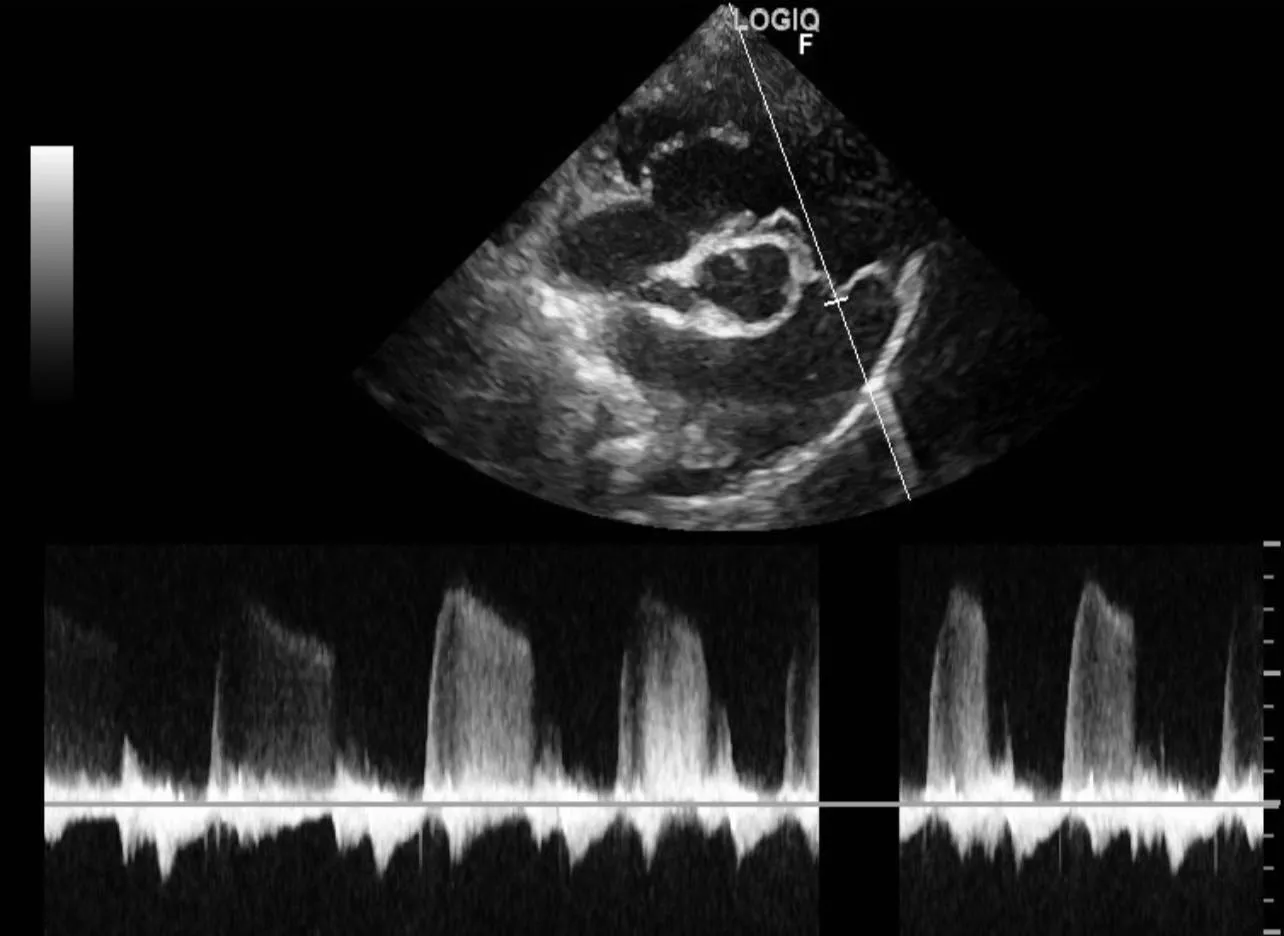

🫀第三步: 心臟超音波/心電圖檢查,診斷左右心房嚴重擴張、二尖瓣與三尖瓣逆流與肺高壓問題。

🫀第三步: 心臟超音波/心電圖檢查,診斷左右心房嚴重擴張、二尖瓣與三尖瓣逆流與肺高壓問題。